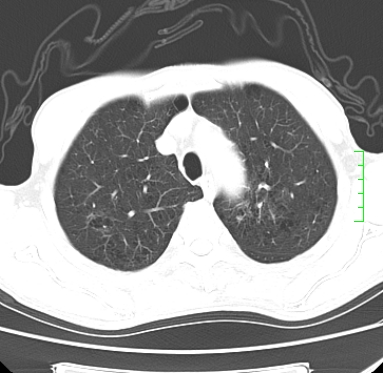

肿块周围可见局限性气肿,考虑肺癌可能性大。双肺上叶继发型肺结核。

指套征,强化明显,近侧肺组织局限性肺气肿,考虑支气管类癌,慢支、肺气肿、双上陈旧性tb、冠脉钙化。

1)考虑右肺下叶周围型肺癌。2)右肺上叶及左肺感染性病变(结核可能)。3)肺气肿。4)冠状动脉钙化。